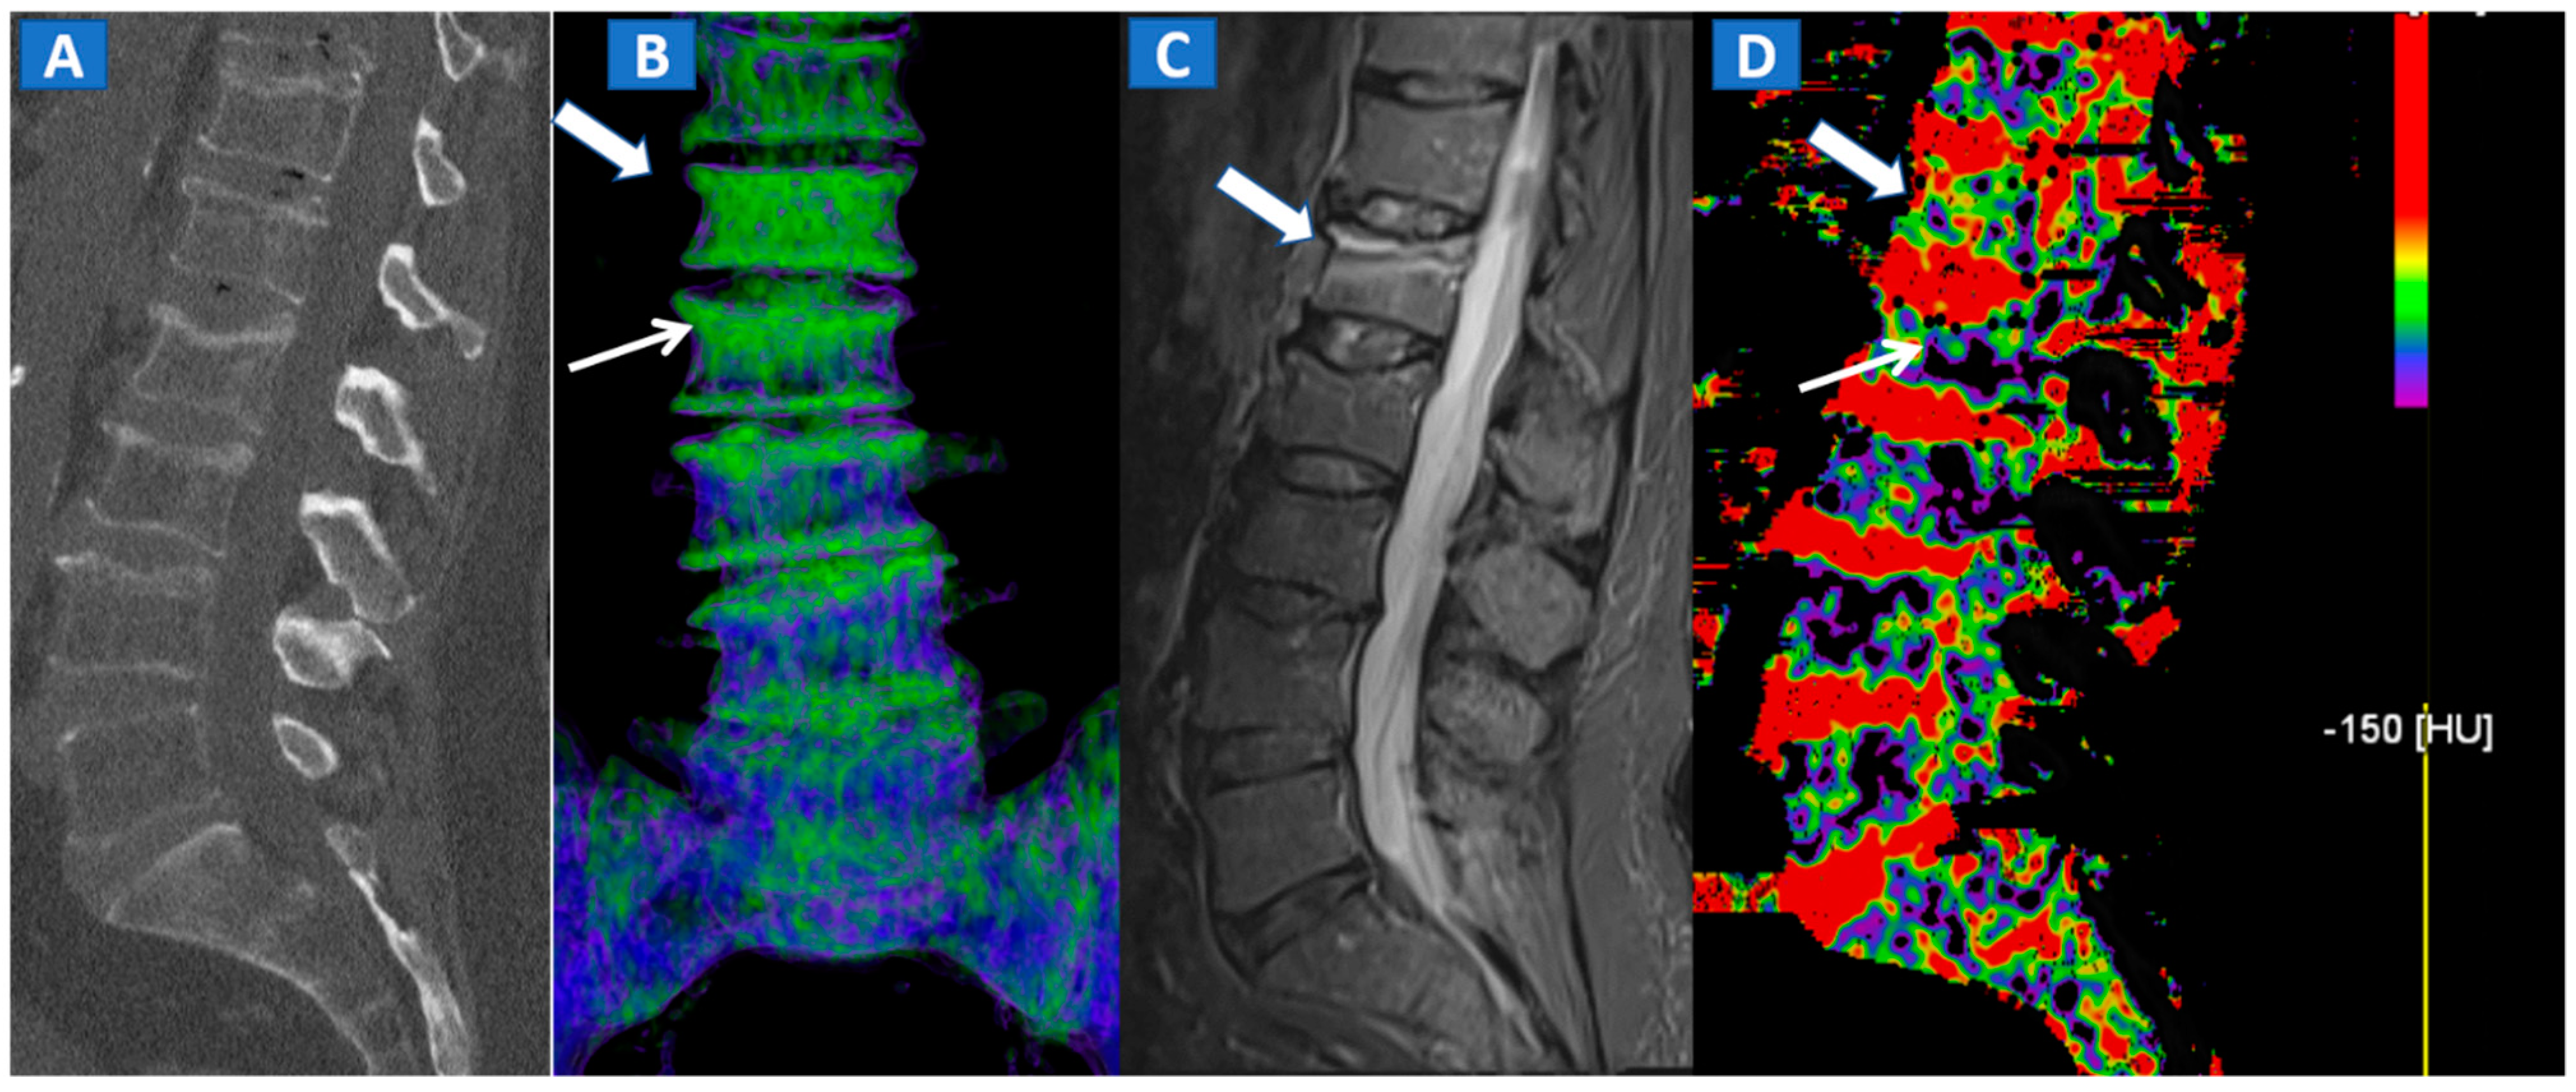

DECT 3D images are usually evaluated first, coding BME in shades of green and coding normal bone in blue (Figure 1). These images serve to provide a clear visual overview of the whole anatomical area, prior to any focus on specific findings. 3D images are usually more sensitive for depicting BME than 2D images (Figure 2). 2D images are analyzed by super-imposing the DE-specific information onto conventional grayscale morphological images (thickness, 1 mm; increment, 1 mm). Usually, a color lookup table is applied, which codes BME in shades ranging from green-yellow to orange-red (Figure 1C), with a range of densities set between −150 and 100 HU (Figure 1C). Superimposed color-coded maps are utilized only when density values are above the −50 HU cut-off. This approach can be useful in distinguishing between severe and mild BME (Figure 2). Additional windowing can also be carried out by increasing or decreasing the level of super-imposition of color-coded images in order to confirm or rule out subtler findings (Figure 2).

Figure 2.

A 62-year-old female with traumatic low back pain following a fall. On the sagittal standard 1 mm CT image (A) it is not possible to identify the fresh fracture. On the coronal 3D DECT image (B), BME of the L1 vertebral body is coded in green (thick arrow), with some mild oedema depicted on the L2 superior endplate (thin arrow). On the sagittal STIR MRI image (C), a fresh fracture of the L1 body is confirmed, with mild oedema located close to the superior endplate (thick arrow). There is no BME of the L2 body apparent on the STIR MRI image. On the corresponding 2D DECT image (D), the maximum level of superimposition of color-coded maps was used to confirm the presence of mild oedema on the L1 vertebral body (thick arrow) and to rule out the presence of significant oedema on the L2 body (thin arrow), thus avoiding a false positive finding.

However, in selected cases, for example in those of bone sclerosis, an alternative and widely used color-coding method, whereby spared bone is represented in violet and BME in shades of green, is preferred; this highlights an important pitfall of DECT [3,7,8]. Sclerosis is often identified on the acetabular roof, especially in patients suffering from degenerative osteoarthritis of the hip, or near to the pubis and sacroiliac joints, in the subchondral areas of knee and ankle, such as the tibial plateaus and talar dome, and adjacent to cortical bone in the upper extremities. Bone sclerosis can generate false positive findings, by locally increasing CT numbers (Figure 2), and can lead to false negative findings, due to excessive subtraction processes that can hinder BME detection. By slightly and progressively increasing the threshold for BME detection, however, it is sometimes possible to detect tiny areas of subchondral BME. In such cases, the parallel evaluation of standard CT images may help to delineate the distribution of sclerosis in expected areas, reducing the risk of misdiagnosis (Figure 3). Additionally, a comparison of the symptomatic and asymptomatic side can help confirm BME of the hip (Figure 3), or in cases where both an affected and unaffected joint are available in the FOV. In more difficult cases, the parameters may be adjusted initially to remove signs of BME from DECT images, before progressively increasing their visibility. By working on the BME threshold and on the level of super-imposition, it is usually possible to more accurately determine the location and distribution of BME.

4. The Spine

In cases of high-energy trauma, DECT images can help to rule out vertebral oedema, and reduce the reading time (Figure 1). When multiple vertebral fractures are present, DECT can identify fresh fractures that are typically characterized by the presence of BME (Figure 2). Furthermore, high resolution CT images can also be used to evaluate fine anatomical details such as transverse processes or posterior arches.